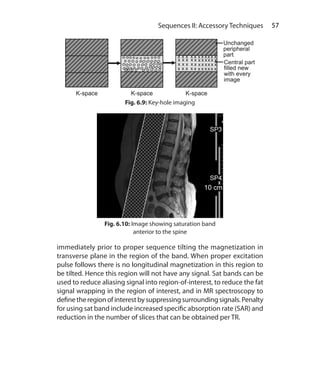

Keyhole Imaging	 56

Saturation Band	 56